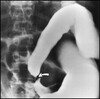

What pathology is shown here?

Esophageal Atresia